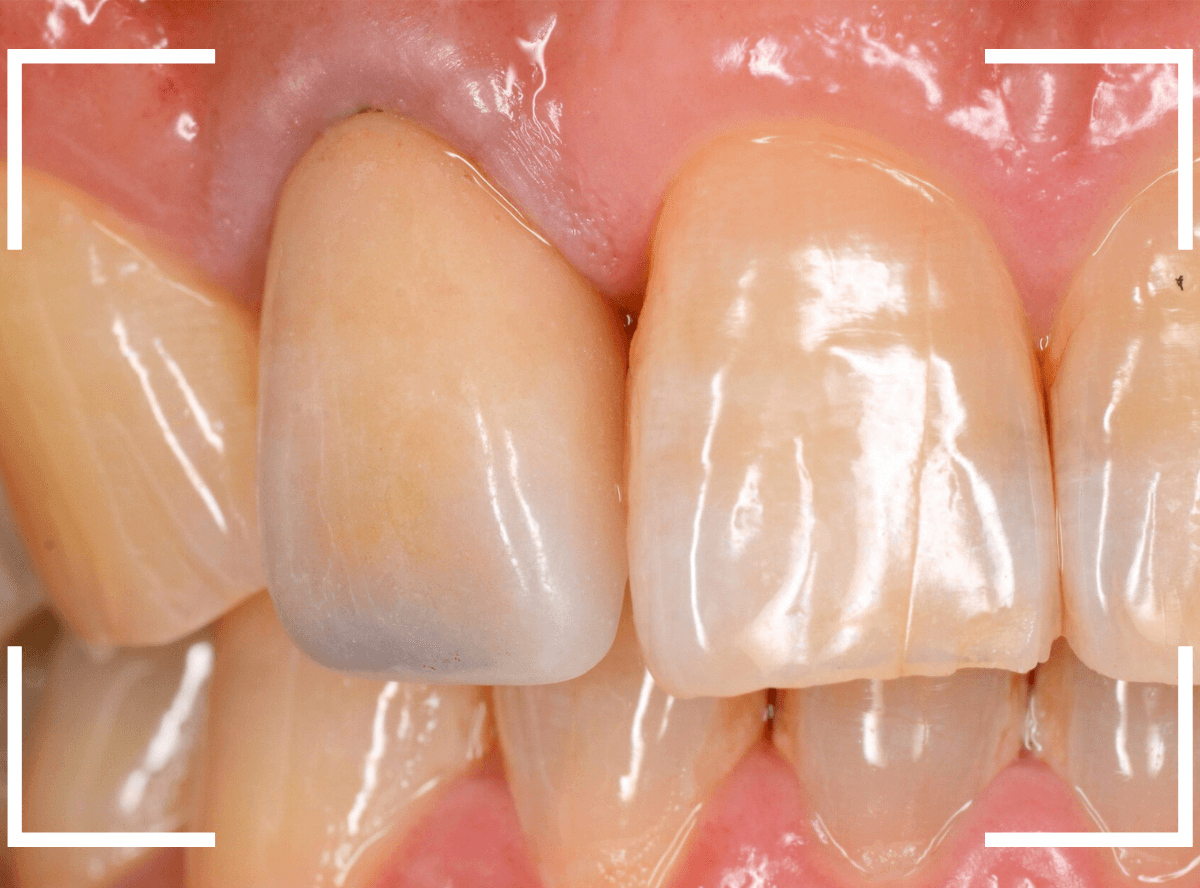

お口の中でsetしたところです。

お口の中に入った状態のビフォーアフターです。

見た目の印象も大きく変わったかと思います。

また、以前のさし歯に比べて、舌触りがとてもよくなったとの感想もいただきました。

恥ずかしながら、私自身もセラミックのさし歯をいれていますが、同じ感想でした。

舌触りが滑らか=汚れがたまりづらく、虫歯や歯周病になりづらい、という健康上のメリットも大きいです。